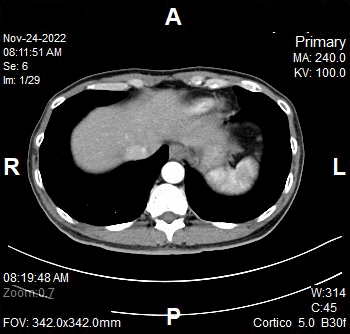

Nephrographic Phase

- Plan the Scan FOV (SFOV) box at topogram image.

- Set the top line at the upper abdomen.

- Set the bottom line at inferior ischial rami.

- Ensure the lateral line to cover patient’s body outline.

- Remind the patient before scanning as the breathing instruction will be given.

- Delay after cortico phase: 35 seconds (enhancement of renal parenchyma including medulla).

Reconstruction of Nephrographic Phase